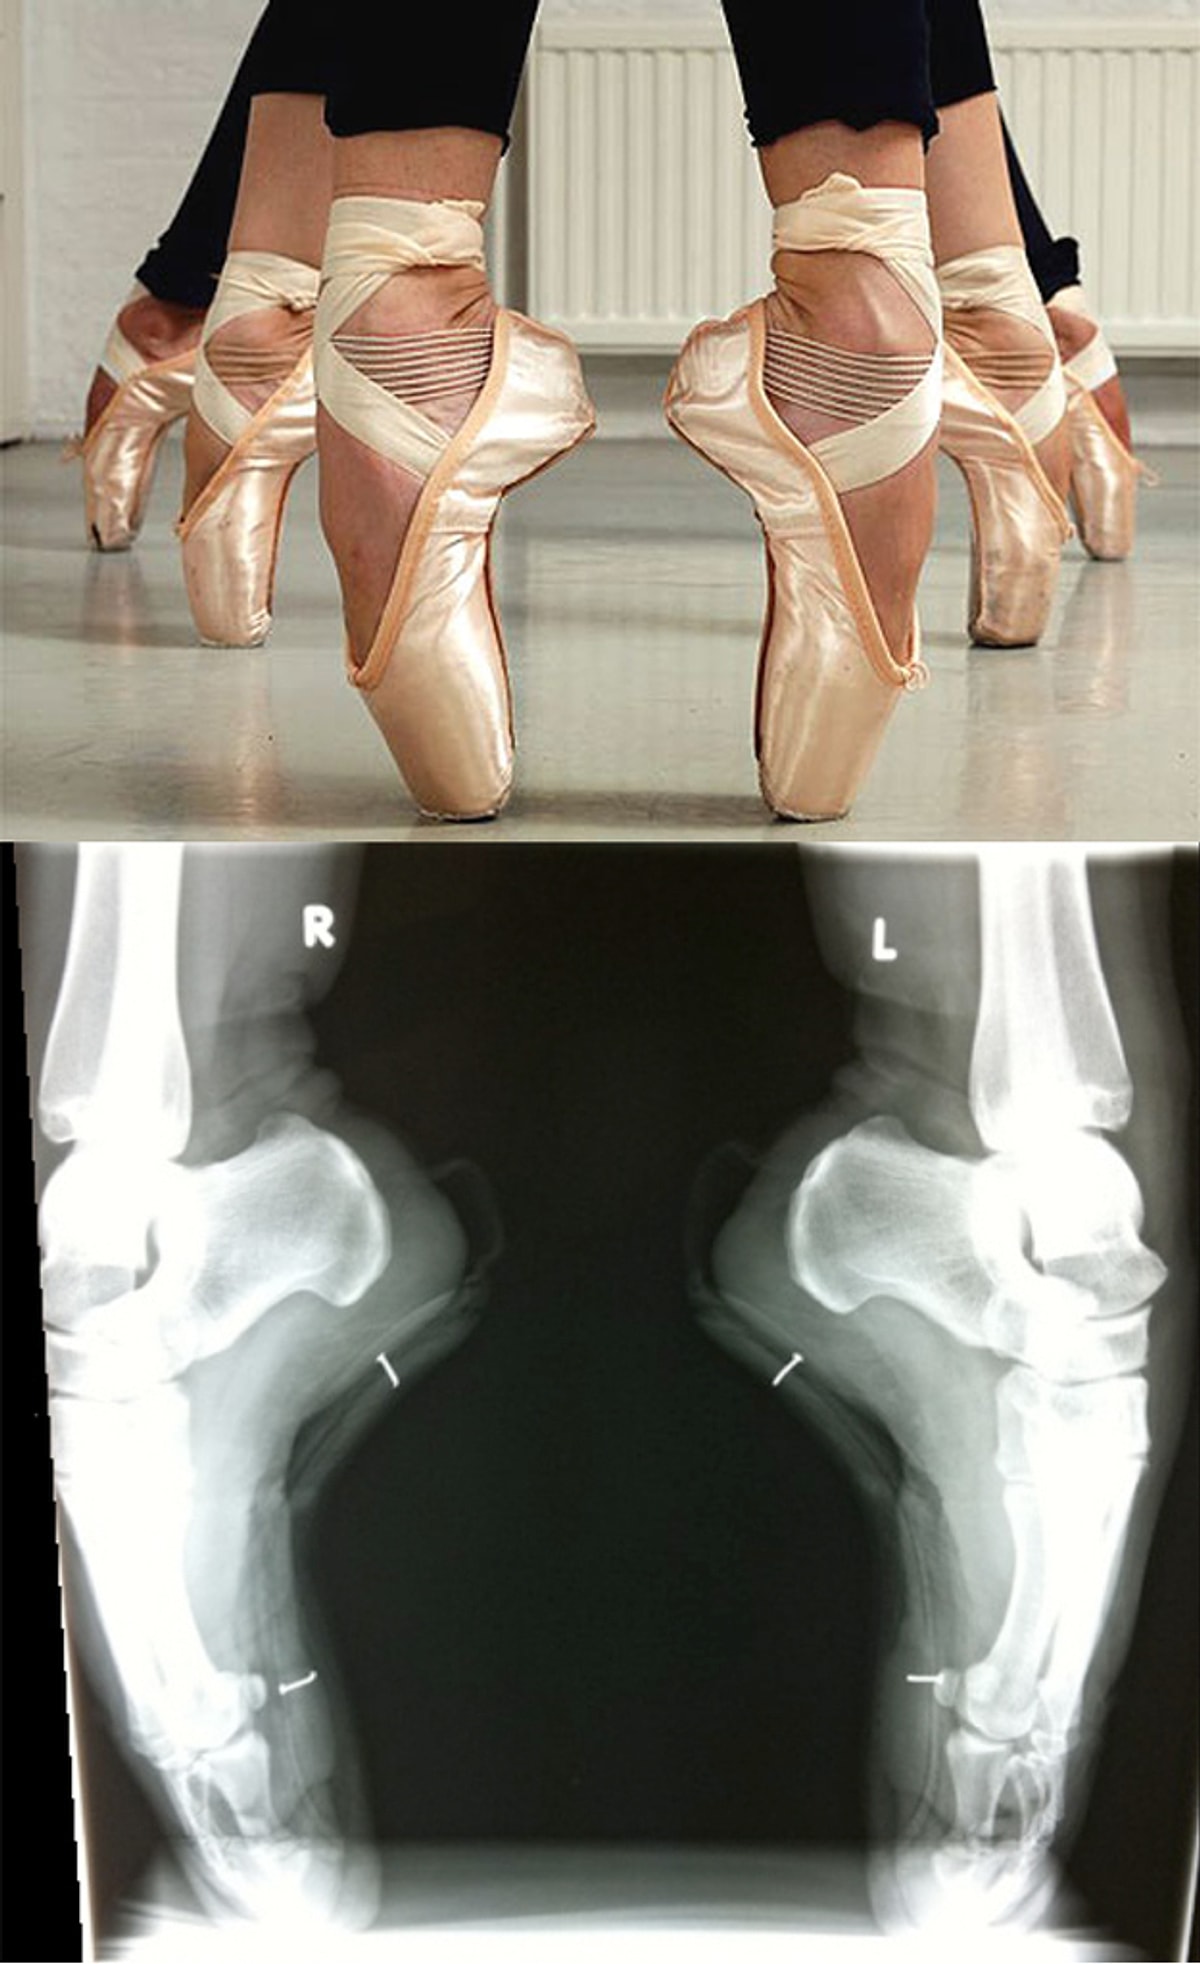

Пальцы Балерины Босиком Фото